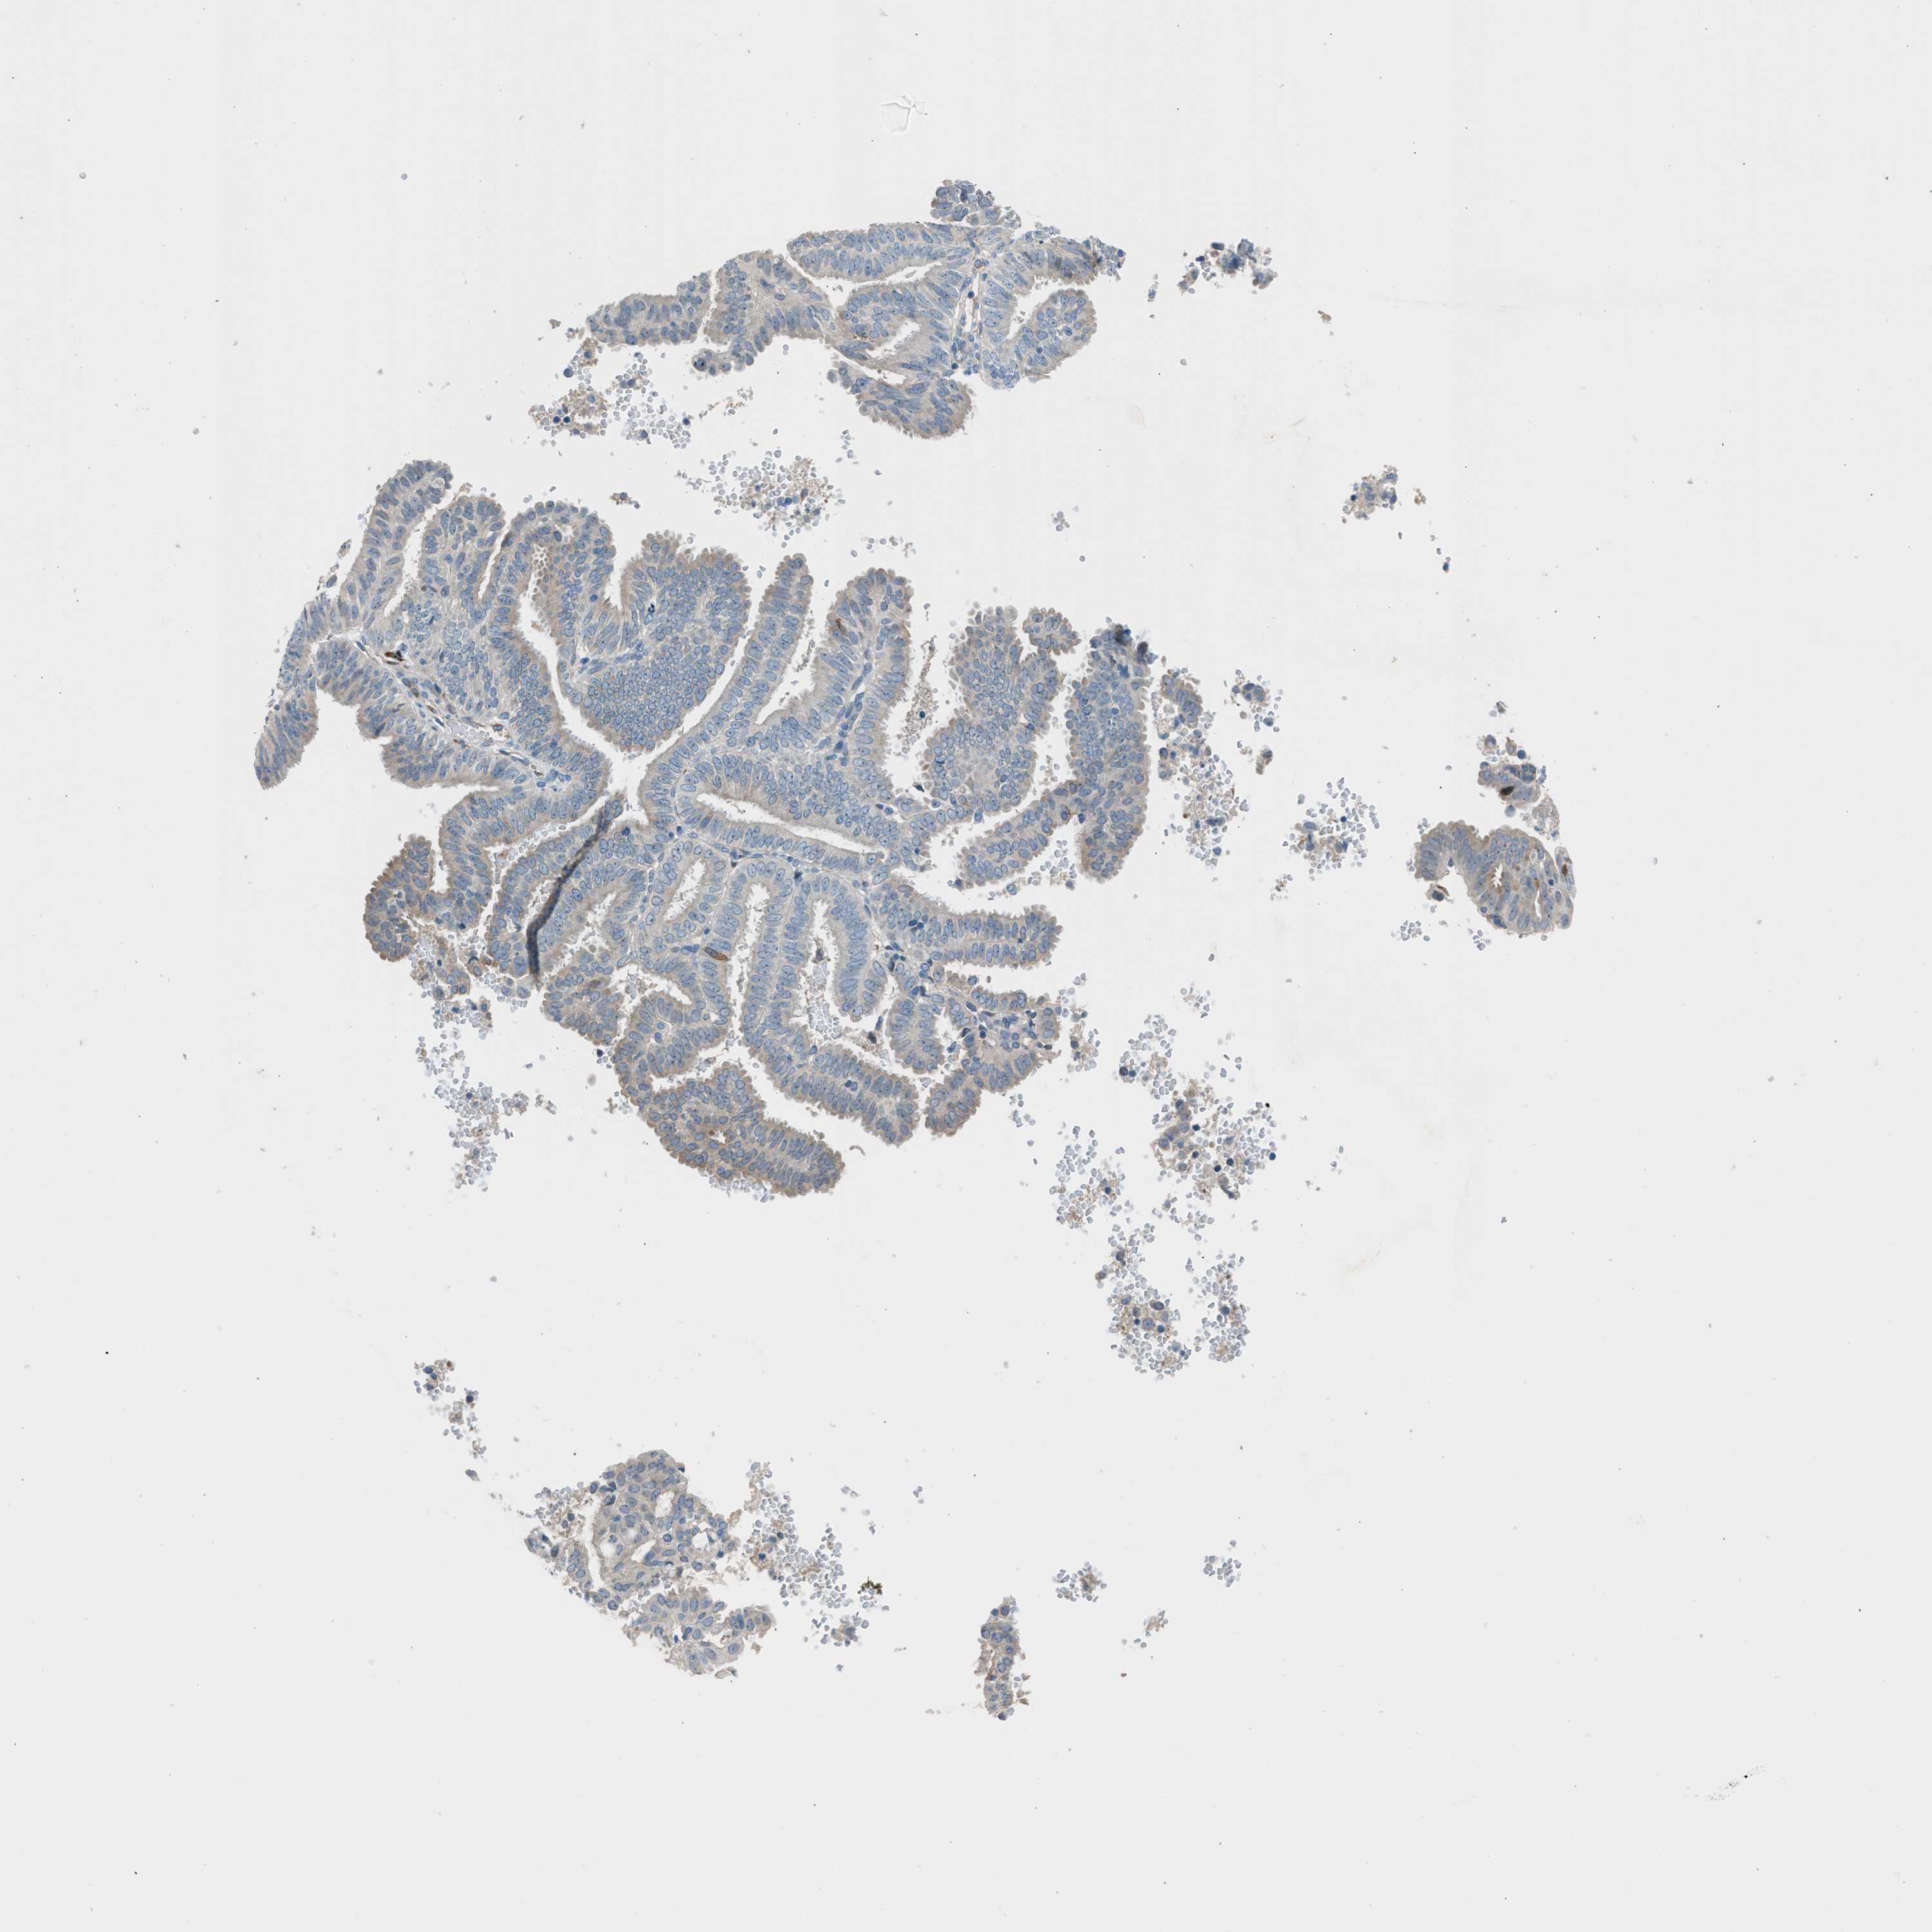

ENDOMETRIAL CANCER - Protein expressioni

A mouse-over function shows sample information and annotation data. Click on an image to view it in a full screen mode. Samples can be filtered based on level of antibody staining by selecting one or several of the following categories: high, medium, low and not detected. The assay and annotation is described here.

Note that samples used for immunohistochemistry by the Human Protein Atlas do not correspond to samples in the TCGA dataset.

Antibody stainingi

Antibody staining in the annotated cell types in the current human tissue is reported as not detected, low, medium, or high, based on conventional immunohistochemistry profiling in selected tissues. This score is based on the combination of the staining intensity and fraction of stained cells.

Each image is clickable and will lead to virtual microscopy that enables deeper exploration of all samples and also displays staining intensity scores, fraction scores and subcellular localization as well as patient and tissue information for each sample.

Antibody HPA016812

Staining

High

Medium

Low

Not detected

Intensity

Strong

Moderate

Weak

Negative

Quantity

>75%

75%-25%

<25%

None

Location

Nuclear

Cytoplasmic/membranous

Cytoplasmic/membranous,nuclear

Adenocarcinoma, NOS